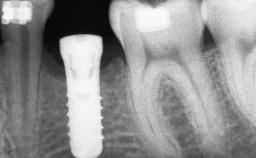

A 45-year-old woman with a completely edentulous maxilla was referred to evaluate the possibility of rehabilitation with an implant-supported prosthesis. This patient was healthy and a non-smoker. She had been wearing a maxillary complete denture opposing a natural mandibular dentition since her twenties. This situation had resulted in progressive resorption of the alveolar ridge, repeatedly creating a need for relining the denture. Twenty years later, despite multiple adaptations and the use of “glues” the denture was unstable and causing the patient psychological and functional discomfort.

Bone Augmentation Horizontal|Sinus Floor Elevation|Staged|Vertical

Bone Volume Deficient vertically or deficient vertically AND horizontally